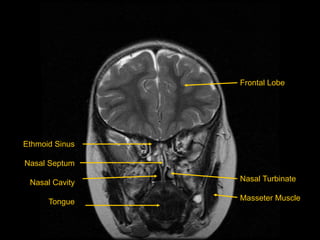

Ethmoid Sinus

Nasal Septum

Nasal Cavity

Tongue

Frontal Lobe

Nasal Turbinate

Masseter Muscle